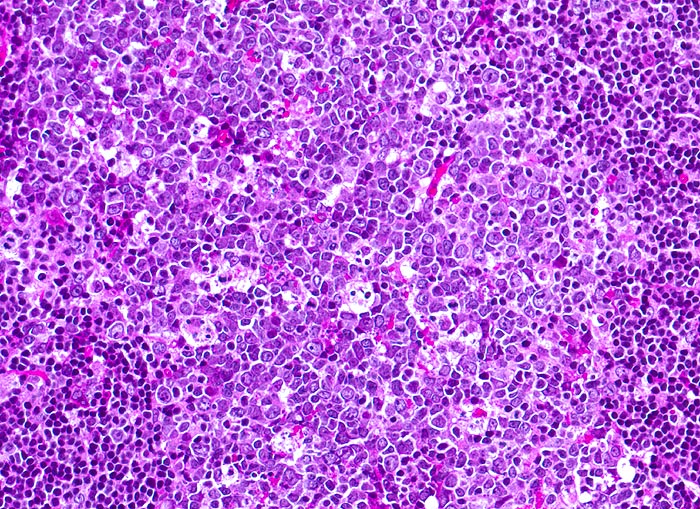

In vielen Fällen entspricht das zytologische Bild bei Mononukleose einer gewöhnlichen reaktiven follikulären Hyperplasie. Seltener findet sich das typische bunte Bild mit vielen plasmozytoiden Zellen und grossen, manchmal doppelkernigen Blasten vom Typ der Zentro-, Immuno- oder Plasmoblasten. Auch Plasmazellen und Granulozyten kommen vor. Stark aktivierte lymphoide Zellen können zur Verwechslung mit einem malignen Lymphom führen.

Die zytologischen Bilder stammen von einem Lymphknoten, die Histologie von einer Tonsille. Die morphologischen Veränderungen bei Mononukleose in diesen beiden Organen sind vergleichbar.